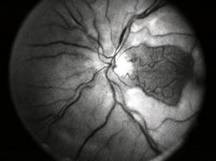

CENTRAL RETINAL VEIN OCCLUSION (CRVO) |

Confluent hemorrhages are the most prominent ophthalmoscopic feature of an acute ischemic central retinal vein occlusion These hemorrhages occur in a wide variety of shapes and sizes; they are usually concentrated in the posterior pole, but may be seen throughout the retina. Many hemorrhages are flame shaped, reflecting the orientation of the nerve fibers. Dot and punctate hemorrhages are interspersed and indicate involvement of the deeper retinal layers. Bleeding may be extensive, erupting through the internal limiting membrane to form a preretinal hemorrhage or extending into the vitreous. Small dot hemorrhages may be seen either isolated or clustered around small venules. The entire venous tree is tortuous, engorged, dilated, and dark. The retina is edematous, particularly in the posterior pole; some of this edema may obscure portions of the retinal vessels. Cotton-wool patches (soft exudates) are often present. The disc margin is blurred or obscured, and the precapillary arterioles appear engorged. Splinter hemorrhages and edema are present on the disc surface and extend into the surrounding retina. The physiologic cup is filled, and the venous pulse is absent. The arterioles, often overlooked because of the other more striking pathologic features, are frequently narrowed. Sometimes in central retinal vein occlusion of acute onset, the fundus picture is less dramatic, and all of the findings previously discussed may be present, but to a lesser degree. Vision depends on extent of macular involvement